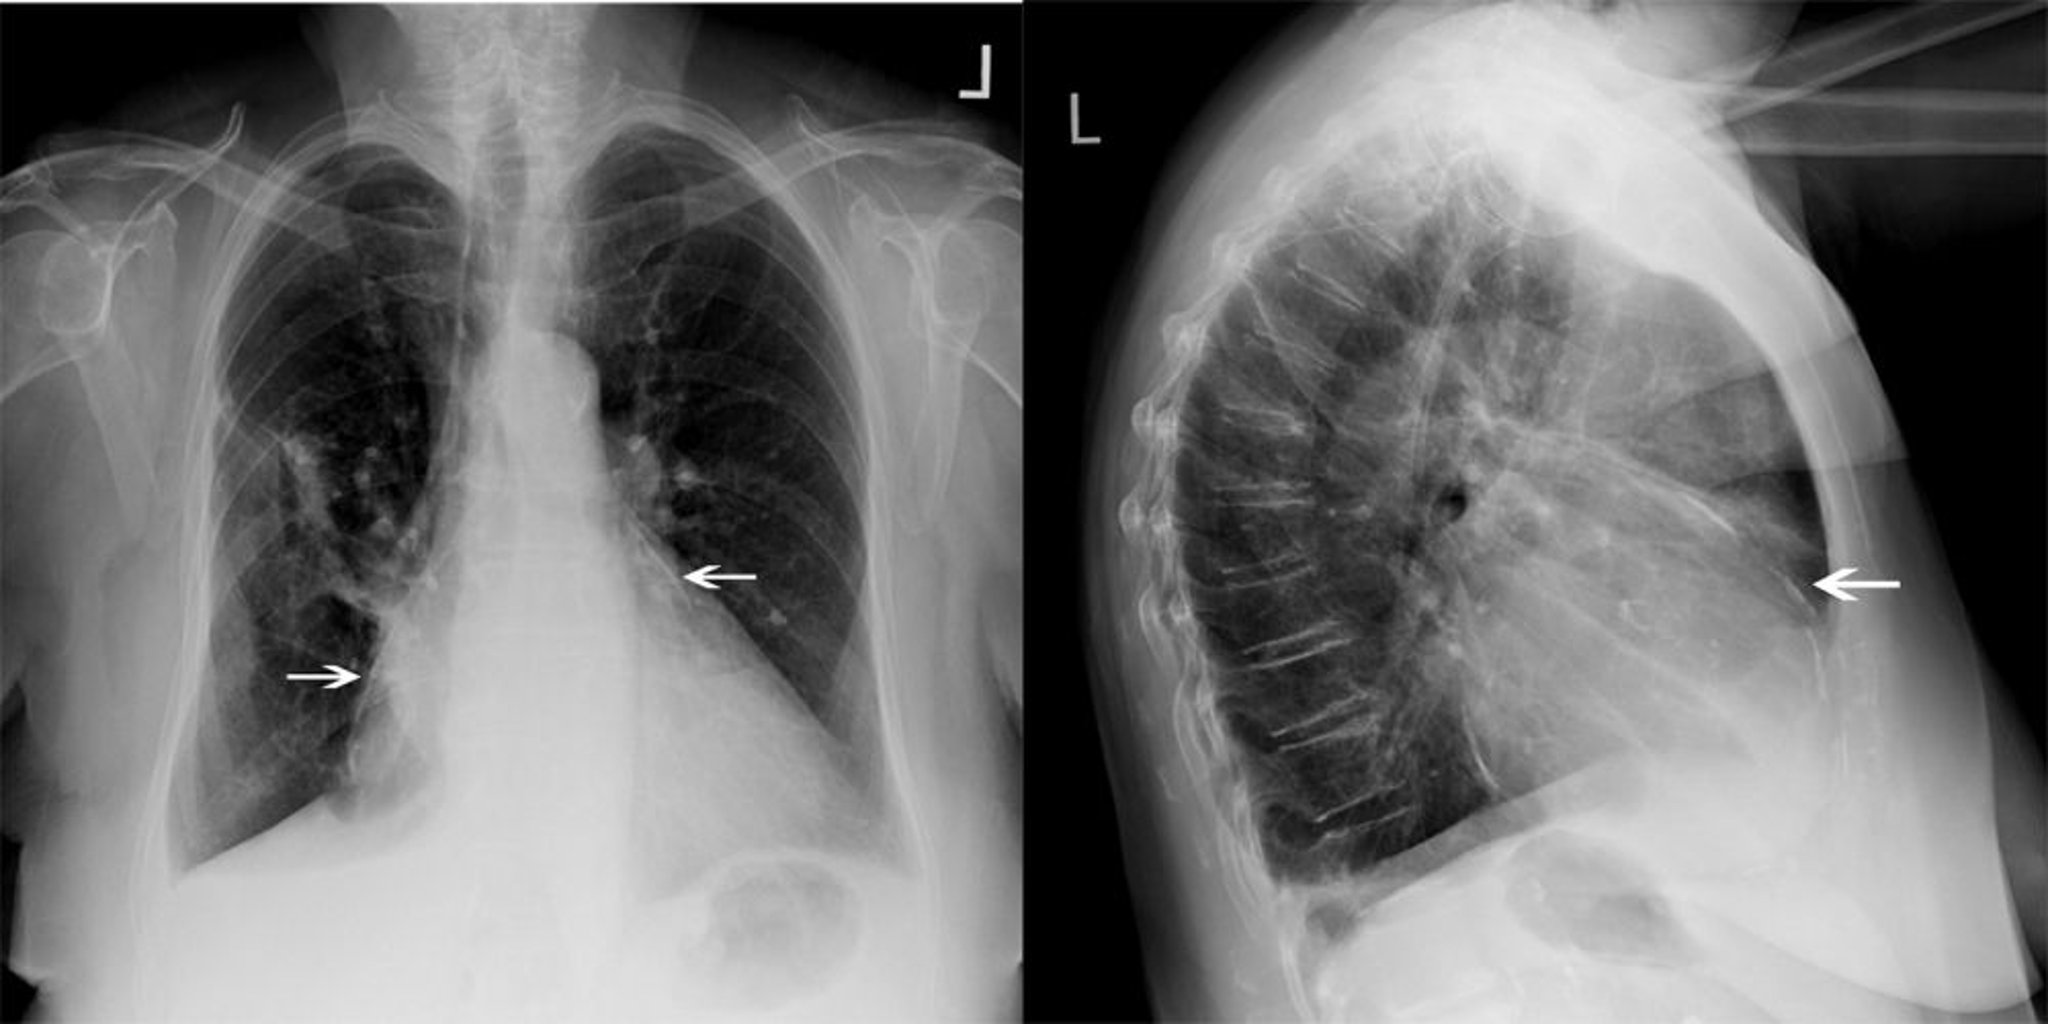

Chest Radiograph of a Patient with Constrictive Pericarditis

This patient with constrictive pericarditis has significant pericardial calcification (white arrows).